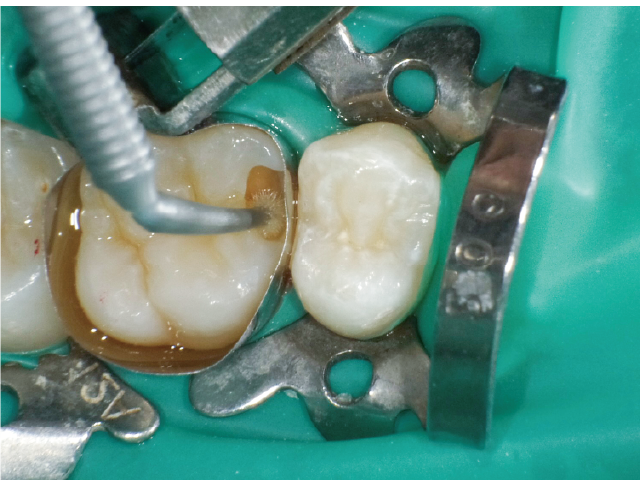

①窩洞形成段階(図1~7)

本症例では、ダイヤモンドの微粒子でコーティングされたエアースケーラーチップを窩洞形態の仕上げに使用。隣在歯の誤切削を防止し、エナメル質の切削断面を歯肉側窩縁までなめらかになるよう仕上げました。

本チップは切削時にストレスが少ない穏やかな振動のエアースケーラー専用のダイヤモンドチップで、切削部となる半球形状の面にのみダイヤモンド砥粒がコーティングされており、背面平坦部は隣在歯を削らないよう平滑になっています(図8、9)。チップの屈曲角度は110°に設定され、窩洞へのアクセスが容易な形状となっています。S67D(アングルの外側)、S68D(アングルの内側)チップは半球状の切削部位が設定され、臼歯部の近遠心両側の窩洞形成に使用が可能です。本症例では、左上6近心隣接面部の窩洞であったため、アングルの外側に半球状の切削部位が設定されている「S67D」を使用しました。これらの器具を使用することにより、頬舌側の隅角部歯質を温存した最小限の規模で窩洞形成を終了、防湿操作および隔壁の設置に移行することができました。